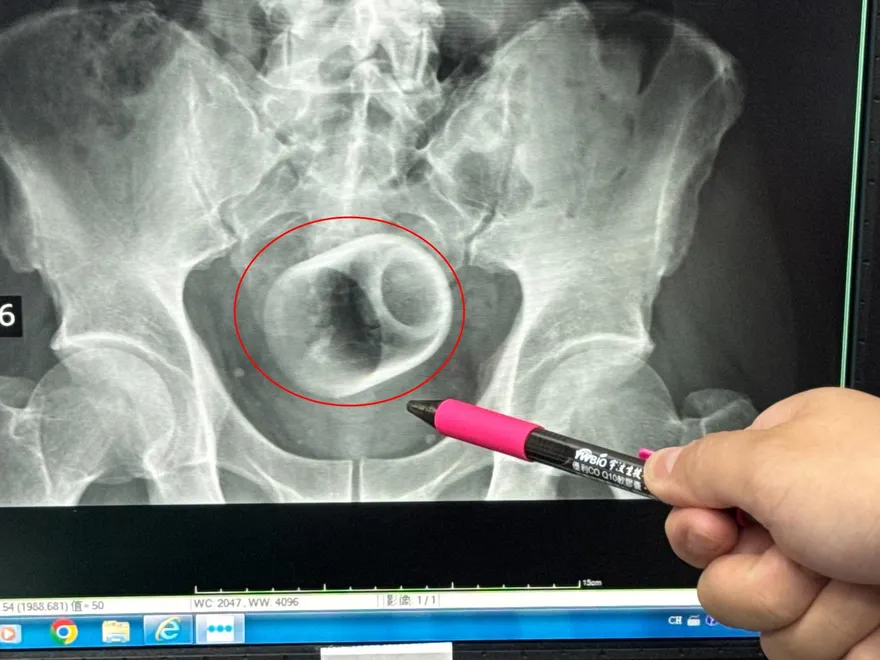

肛門異物

陶瓷杯卡肛門

開腹手術

腸道壞死

肛門括約肌損傷

人工造口

腹腔感染